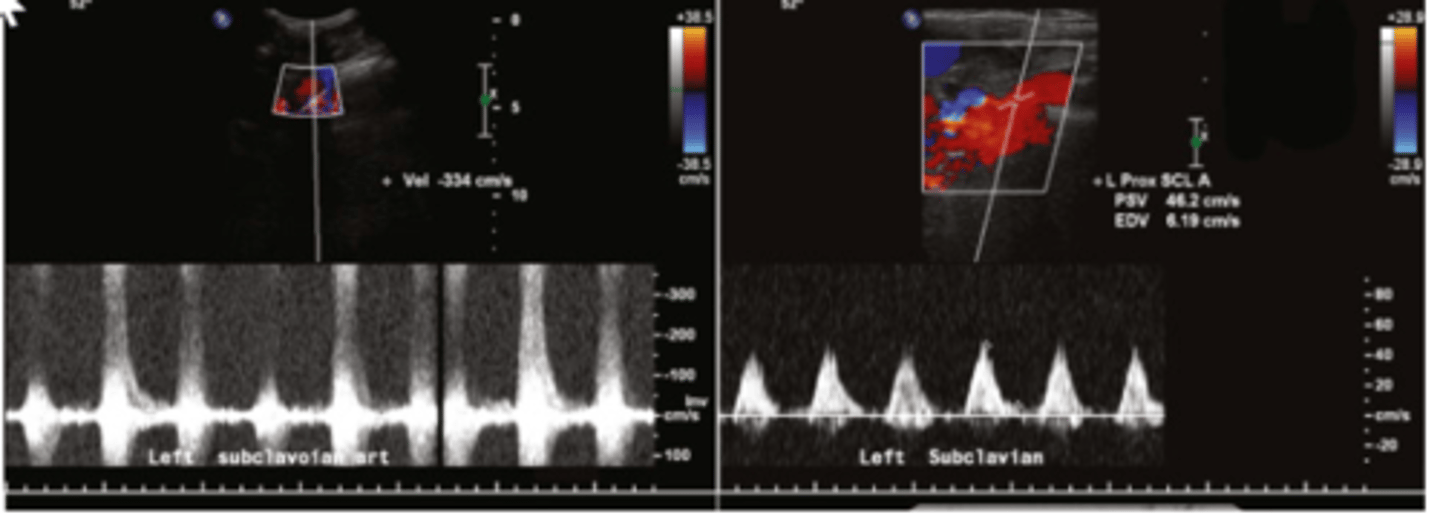

The ultrasound image with a velocity of 334 cm/sec was recorded at the proximal left subclavian artery, the ultrasound image with a velocity of 46/6 cm/sec was recorded at the mid left subclavian artery. What does this exam demonstrate?

>50% stenosis of the proximal subclavian artery